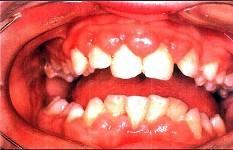

问题 患者,男性,19岁,主诉:前牙牙龈红肿肥大1年余。临床检查:上唇短,上前牙唇侧牙龈边缘及龈乳头增生肥大,覆盖牙冠的1/3,质地较韧。最可能的诊断是 ( )

选项 A.青春期龈炎 B.急性坏死性溃疡性龈炎 C.慢性龈缘炎 D.增生性龈炎 E.牙龈纤维瘤病

答案 D